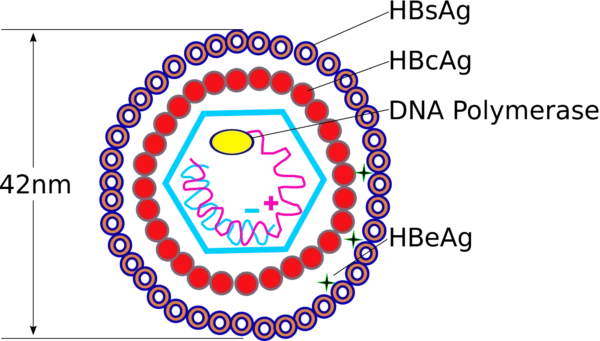

Hepatitis B

Die Hepatitis B ist eine virale Entzündung der Leber. Sie wird hervorgerufen durch das Hepatitis-B-Virus (ein DNA-Virus, Abk. HBV) und wird meist durch Sexual- und Blutkontakt übertragen. Alle Körperflüssigkeiten können das Virus enthalten.